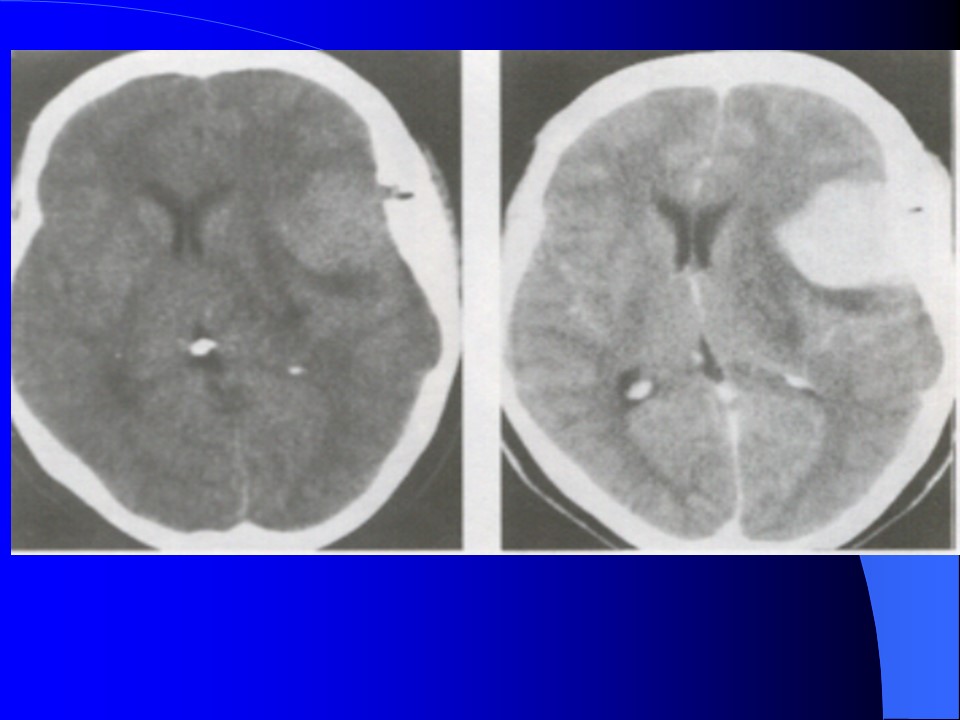

“脑膜瘤的影像学诊断PPT” 的相关文章